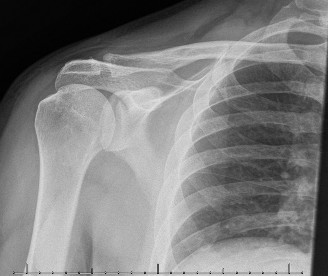

Treat a patient with infected total shoulder arthroplasty? CASE 21 A 70-year-old, right-hand-dominant female presents to clinic complaining of 4 years of gradually worsening chronic right shoulder pain and stiffness. She says the pain is worse at night and with any range of motion, denies a history of trauma, pain in other extremities, or numbness or tingling of the right upper extremity. She notes that her mother suffered from rheumatoid arthritis that affected her shoulder. Physical examination reveals decreased muscle bulk over the right supra- and infraspinatus fossae compared to the contralateral side, limited active and passive ROM, marked weakness with external rotation, and 4+/5 strength with shoulder abduction. X-rays of the right shoulder are shown in Figures 2–58 and 2–59.

Figure 2–58

Figure 2–59

The correct answer is (C). Rotator cuff tear arthropathy consists of a combination of rotator cuff insufficiency, glenohumeral joint degenerative changes, and superior humeral head migration. It is more common in women and also more often found on the dominant side. The patient’s clinical examination with weakened external

rotation and muscle atrophy signaling incompetent supra- and infraspinatus muscles point to rotator cuff insufficiency, and her plain films reveal narrowed glenohumeral joint space as well as superior migration of the humeral head. Choice D is incorrect because, while radiographs would show narrowing of the glenohumeral joint space, they would also likely show numerous osteophytes and posterior wear of the glenoid. Choice B is incorrect because, while adhesive capsulitis does present as decreased active and passive range of motion, the patient’s constellation of symptoms pointing towards rotator cuff insufficiency along with the radiographs make cuff tear arthropathy the more likely choice. Finally, Choice A is incorrect because even though she has a positive family history of rheumatoid arthritis, it is less likely to present only in a single joint. Also, rheumatoid arthritis on radiography appears more as an erosive process without the characteristic superior migration of the humeral head.

The correct answer is (A). Superior migration of the humeral head would be most indicative of chronic rotator cuff insufficiency associated with cuff tear arthropathy, as it is a direct result of the inability of the rotator cuff tendons to help maintain the humerus in its normal position. Acetabularization of the undersurface of the acromion is commonly associated with superior migration of the humeral head found in rotator cuff tear arthropathy, and can be assessed using the Hamada classification, which is based on measurements of the acromiohumeral interval on radiography (Table 2–8). Choices B and C are incorrect because, while narrowed glenohumeral joint space and subchondral sclerosis are associated with rotator cuff arthropathy on radiographs, they indicate degenerative joint changes rather than chronic rotator cuff insufficiency. Choice D is incorrect because it is not a specific sign of rotator cuff arthropathy.